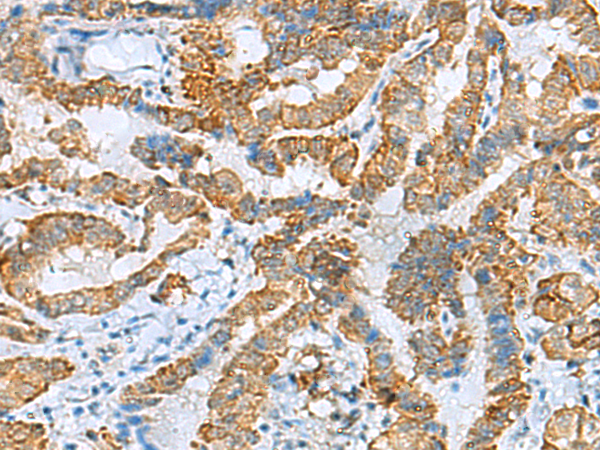

分类: 科研抗体货号: P03359别名: PhLP应用: WB,IHC反应种属: Human, Mouse, Rat